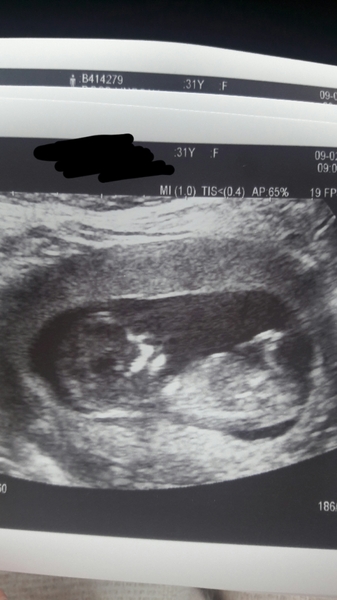

I had my dating scan today I was so worried but everything was fine and baby was flipping and rolling all over the place it wouldn't stay still! Just waiting on results now, nt was 1.4mm so hope that's a good sign.